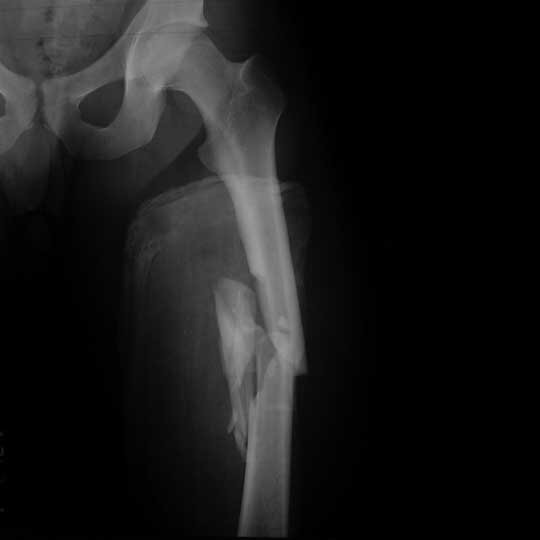

Чуть меньше года назад я попал в сильное ДТП, результатом чего стал закрытый многооскольчатый перелом бедренной кости со смещением (зрелище не из приятных скажу я вам и по ощущениям в принципе тоже).

Снимок после аварии